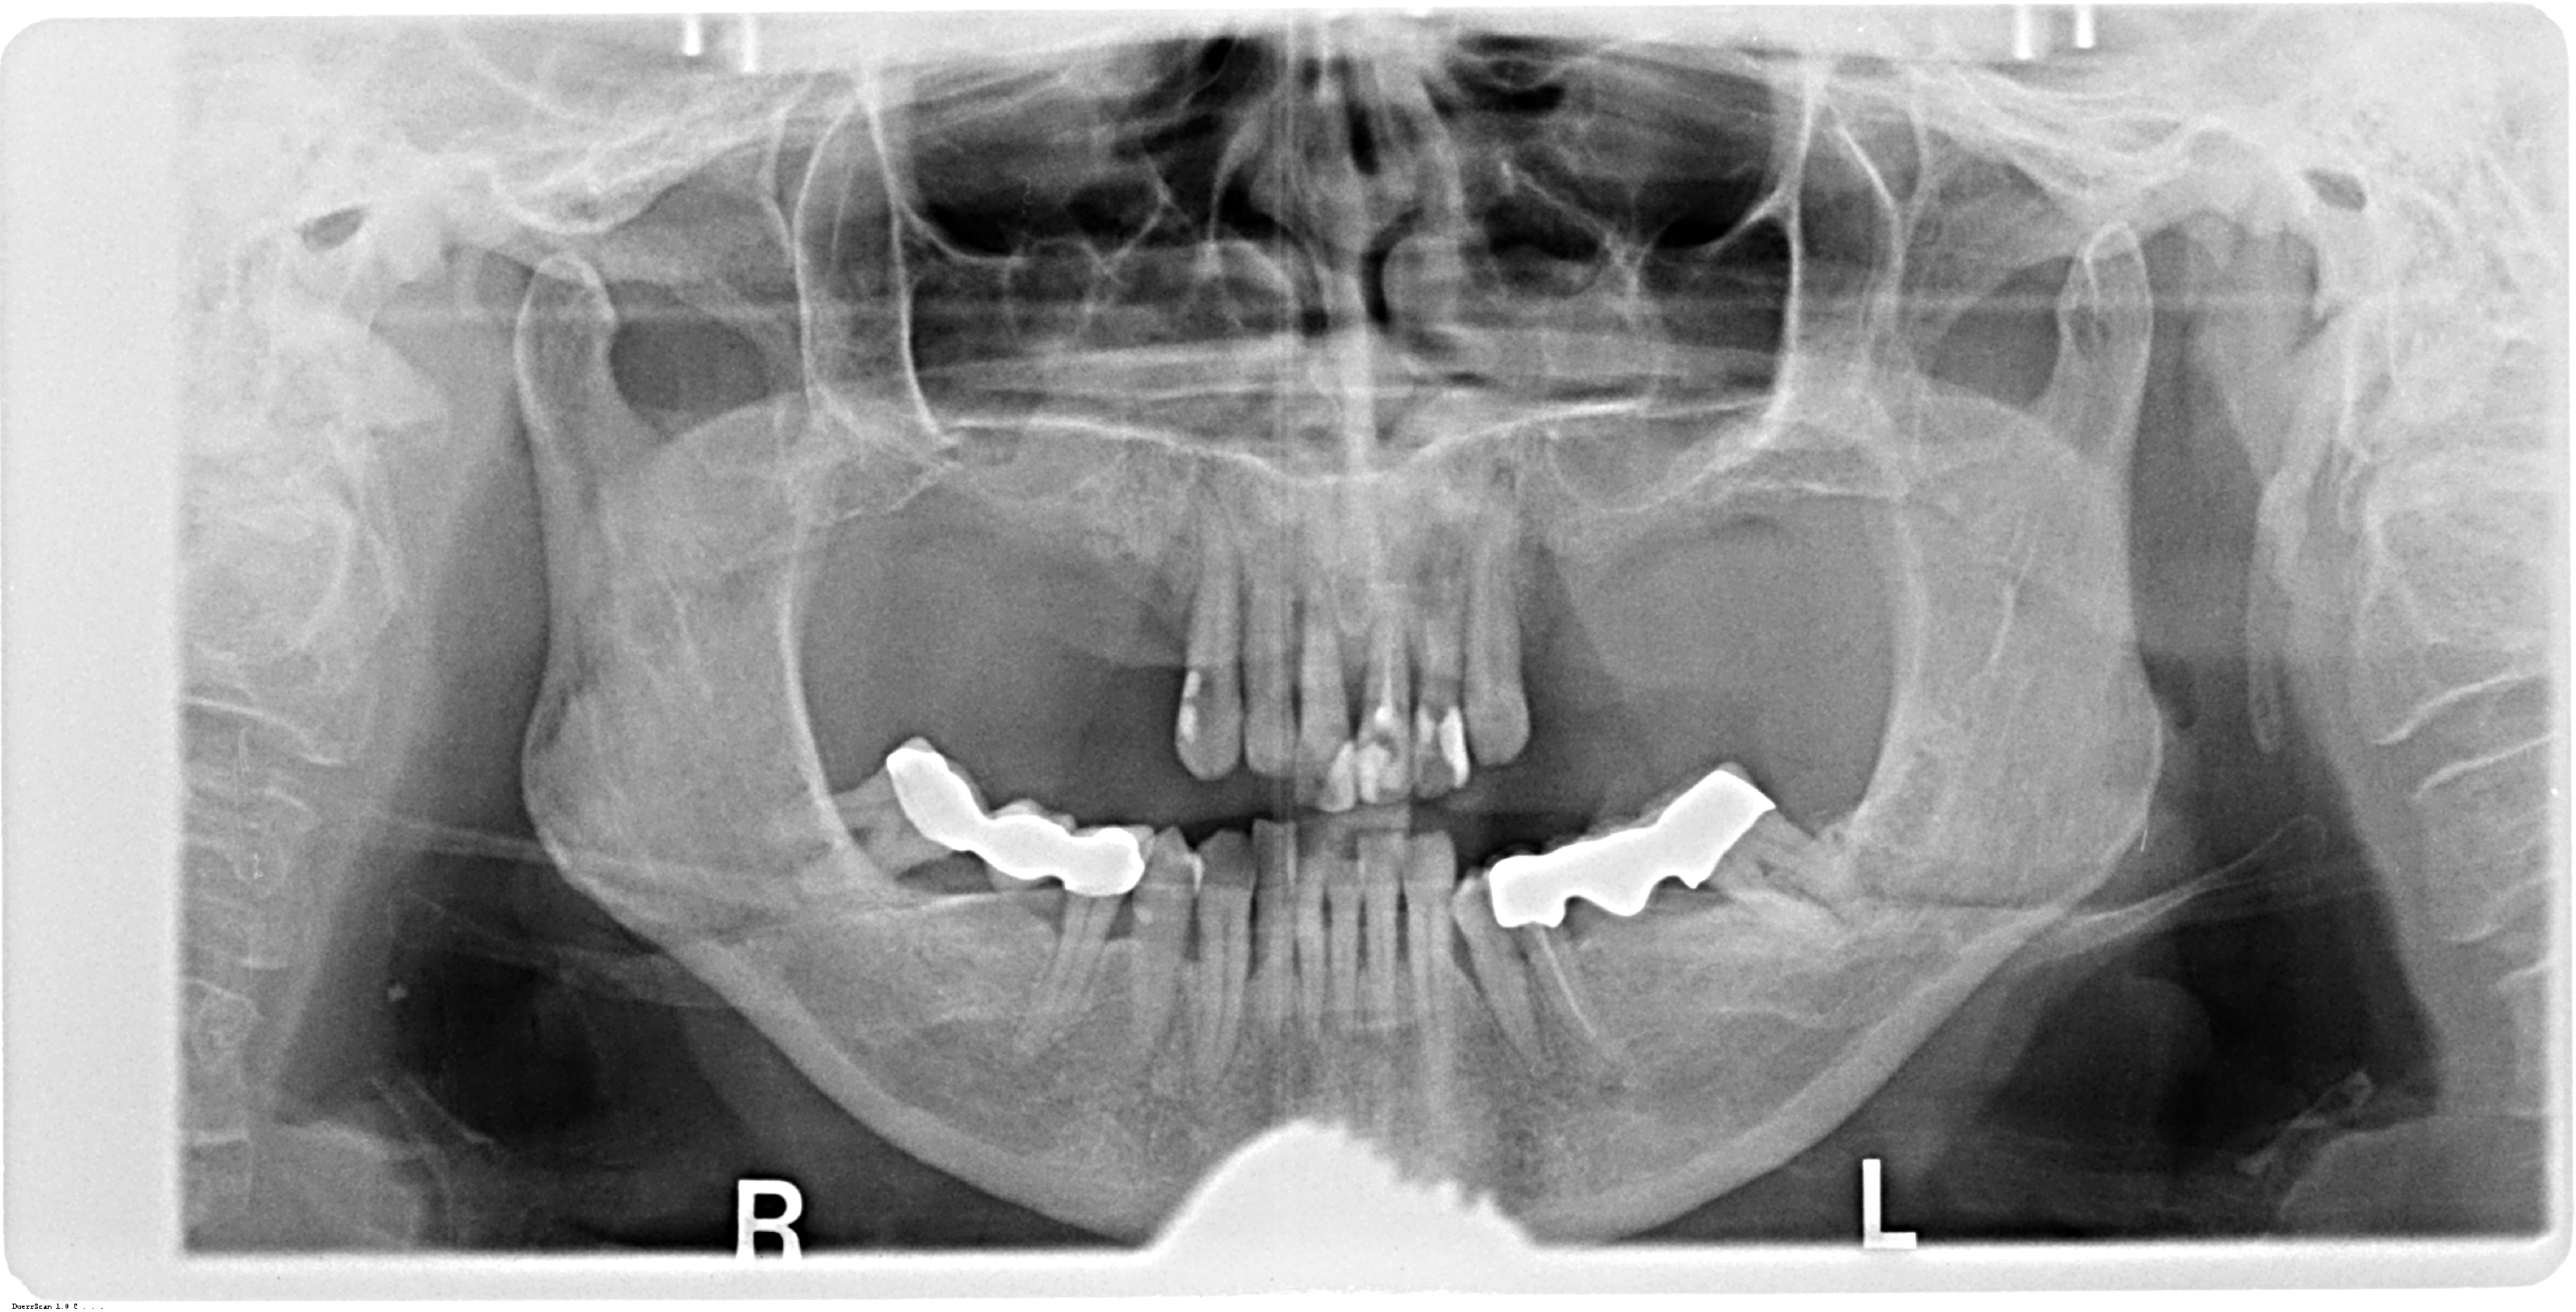

A 67-year-old female patient presented with a severely compromised anterior maxilla. Remaining teeth 13–23 showed advanced bone loss, periodontal breakdown, and a deep bite. The teeth were deemed non-restorable. The patient experienced functional limitations and significant aesthetic concern. Medical history was unremarkable.

Initial diagnostics included CBCT imaging and full-arch intraoral scanning. A digital wax-up with an increased vertical dimension of approximately 2 mm was created to simulate functional and aesthetic improvements. Fully digital implant planning was carried out, and a SMOP tooth supported guide was designed, anchored in the region of the lateral incisors.